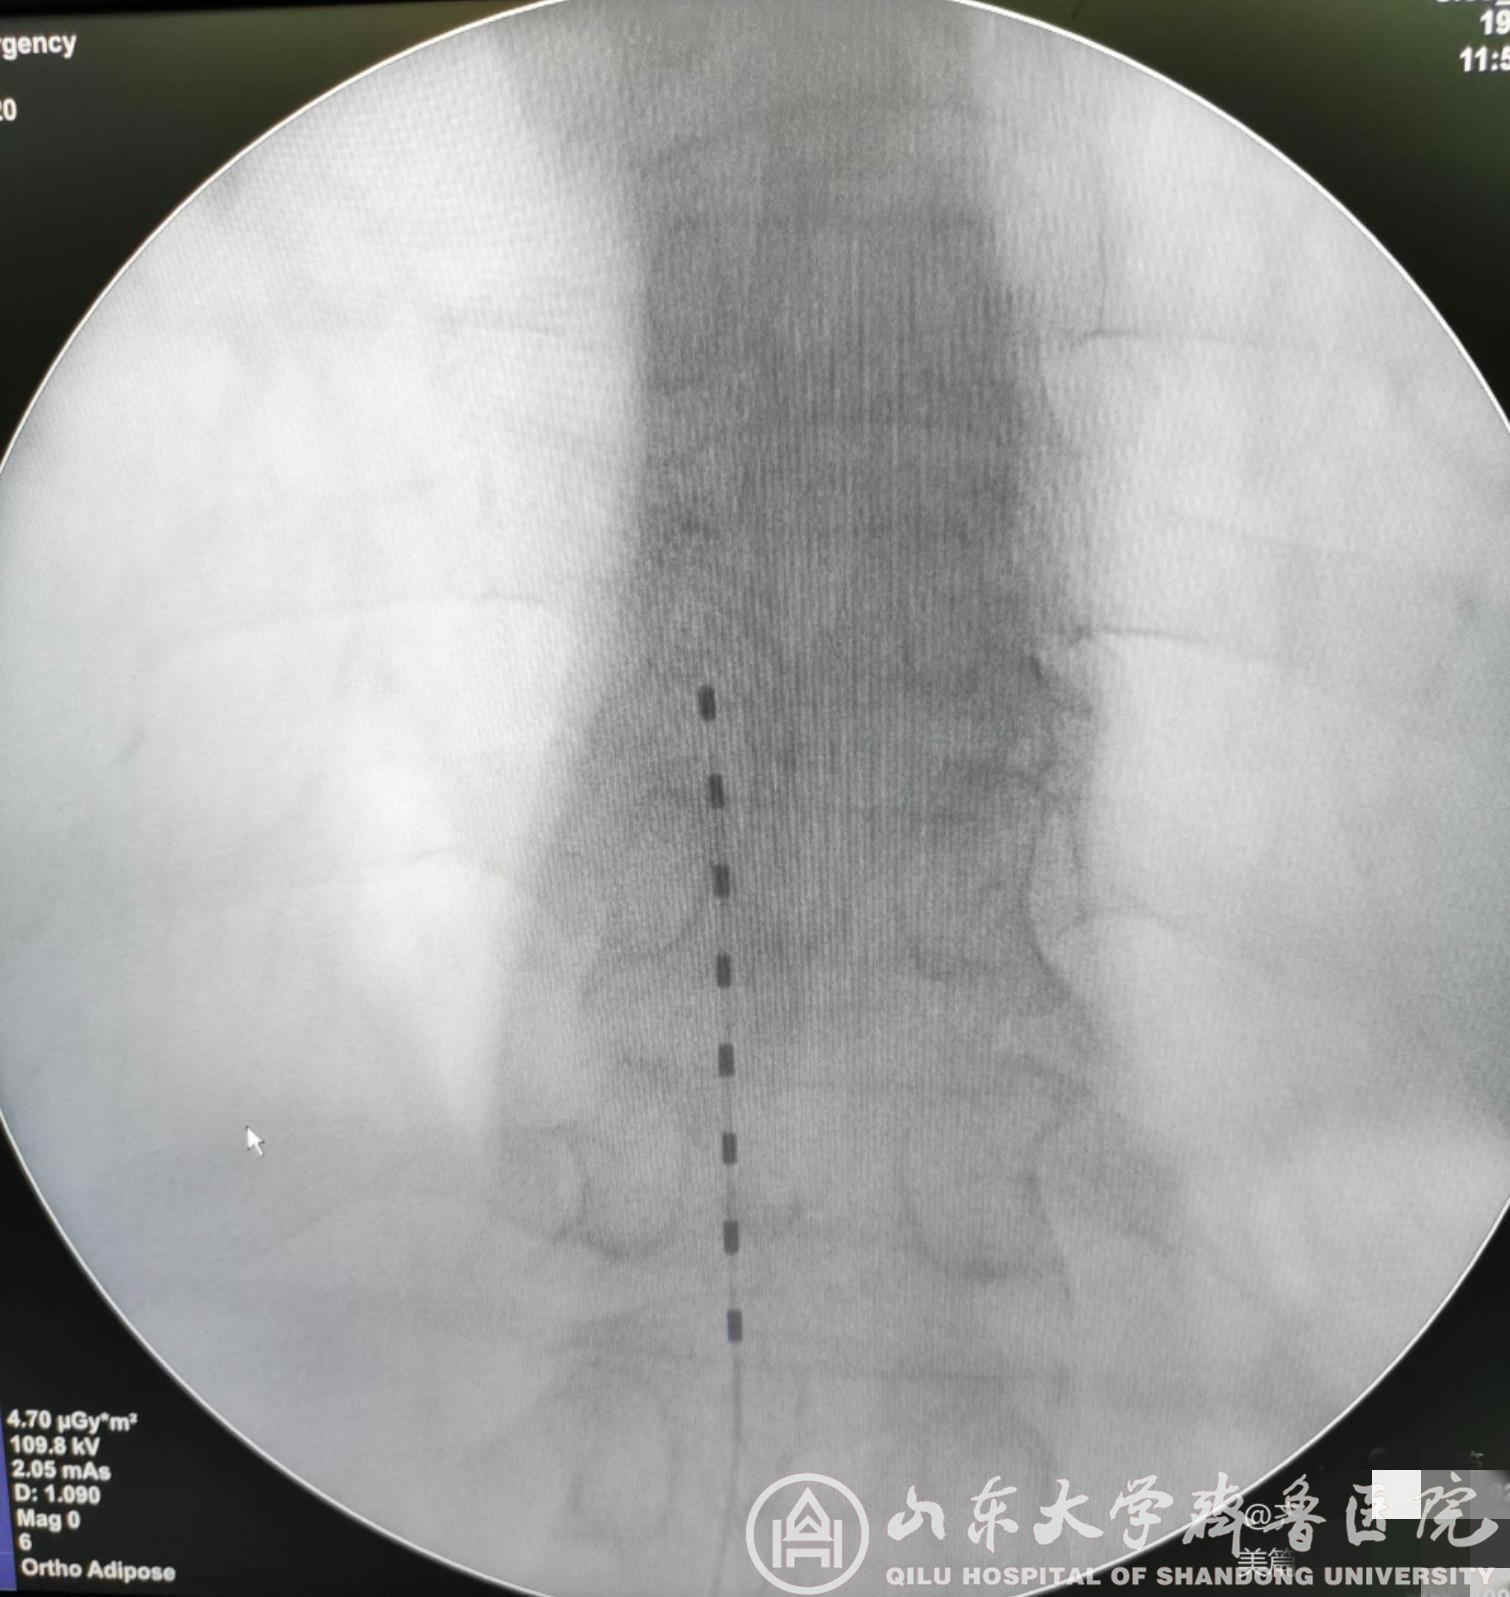

图1.带状疱疹性神经痛患者术后X线检查电极位置良好